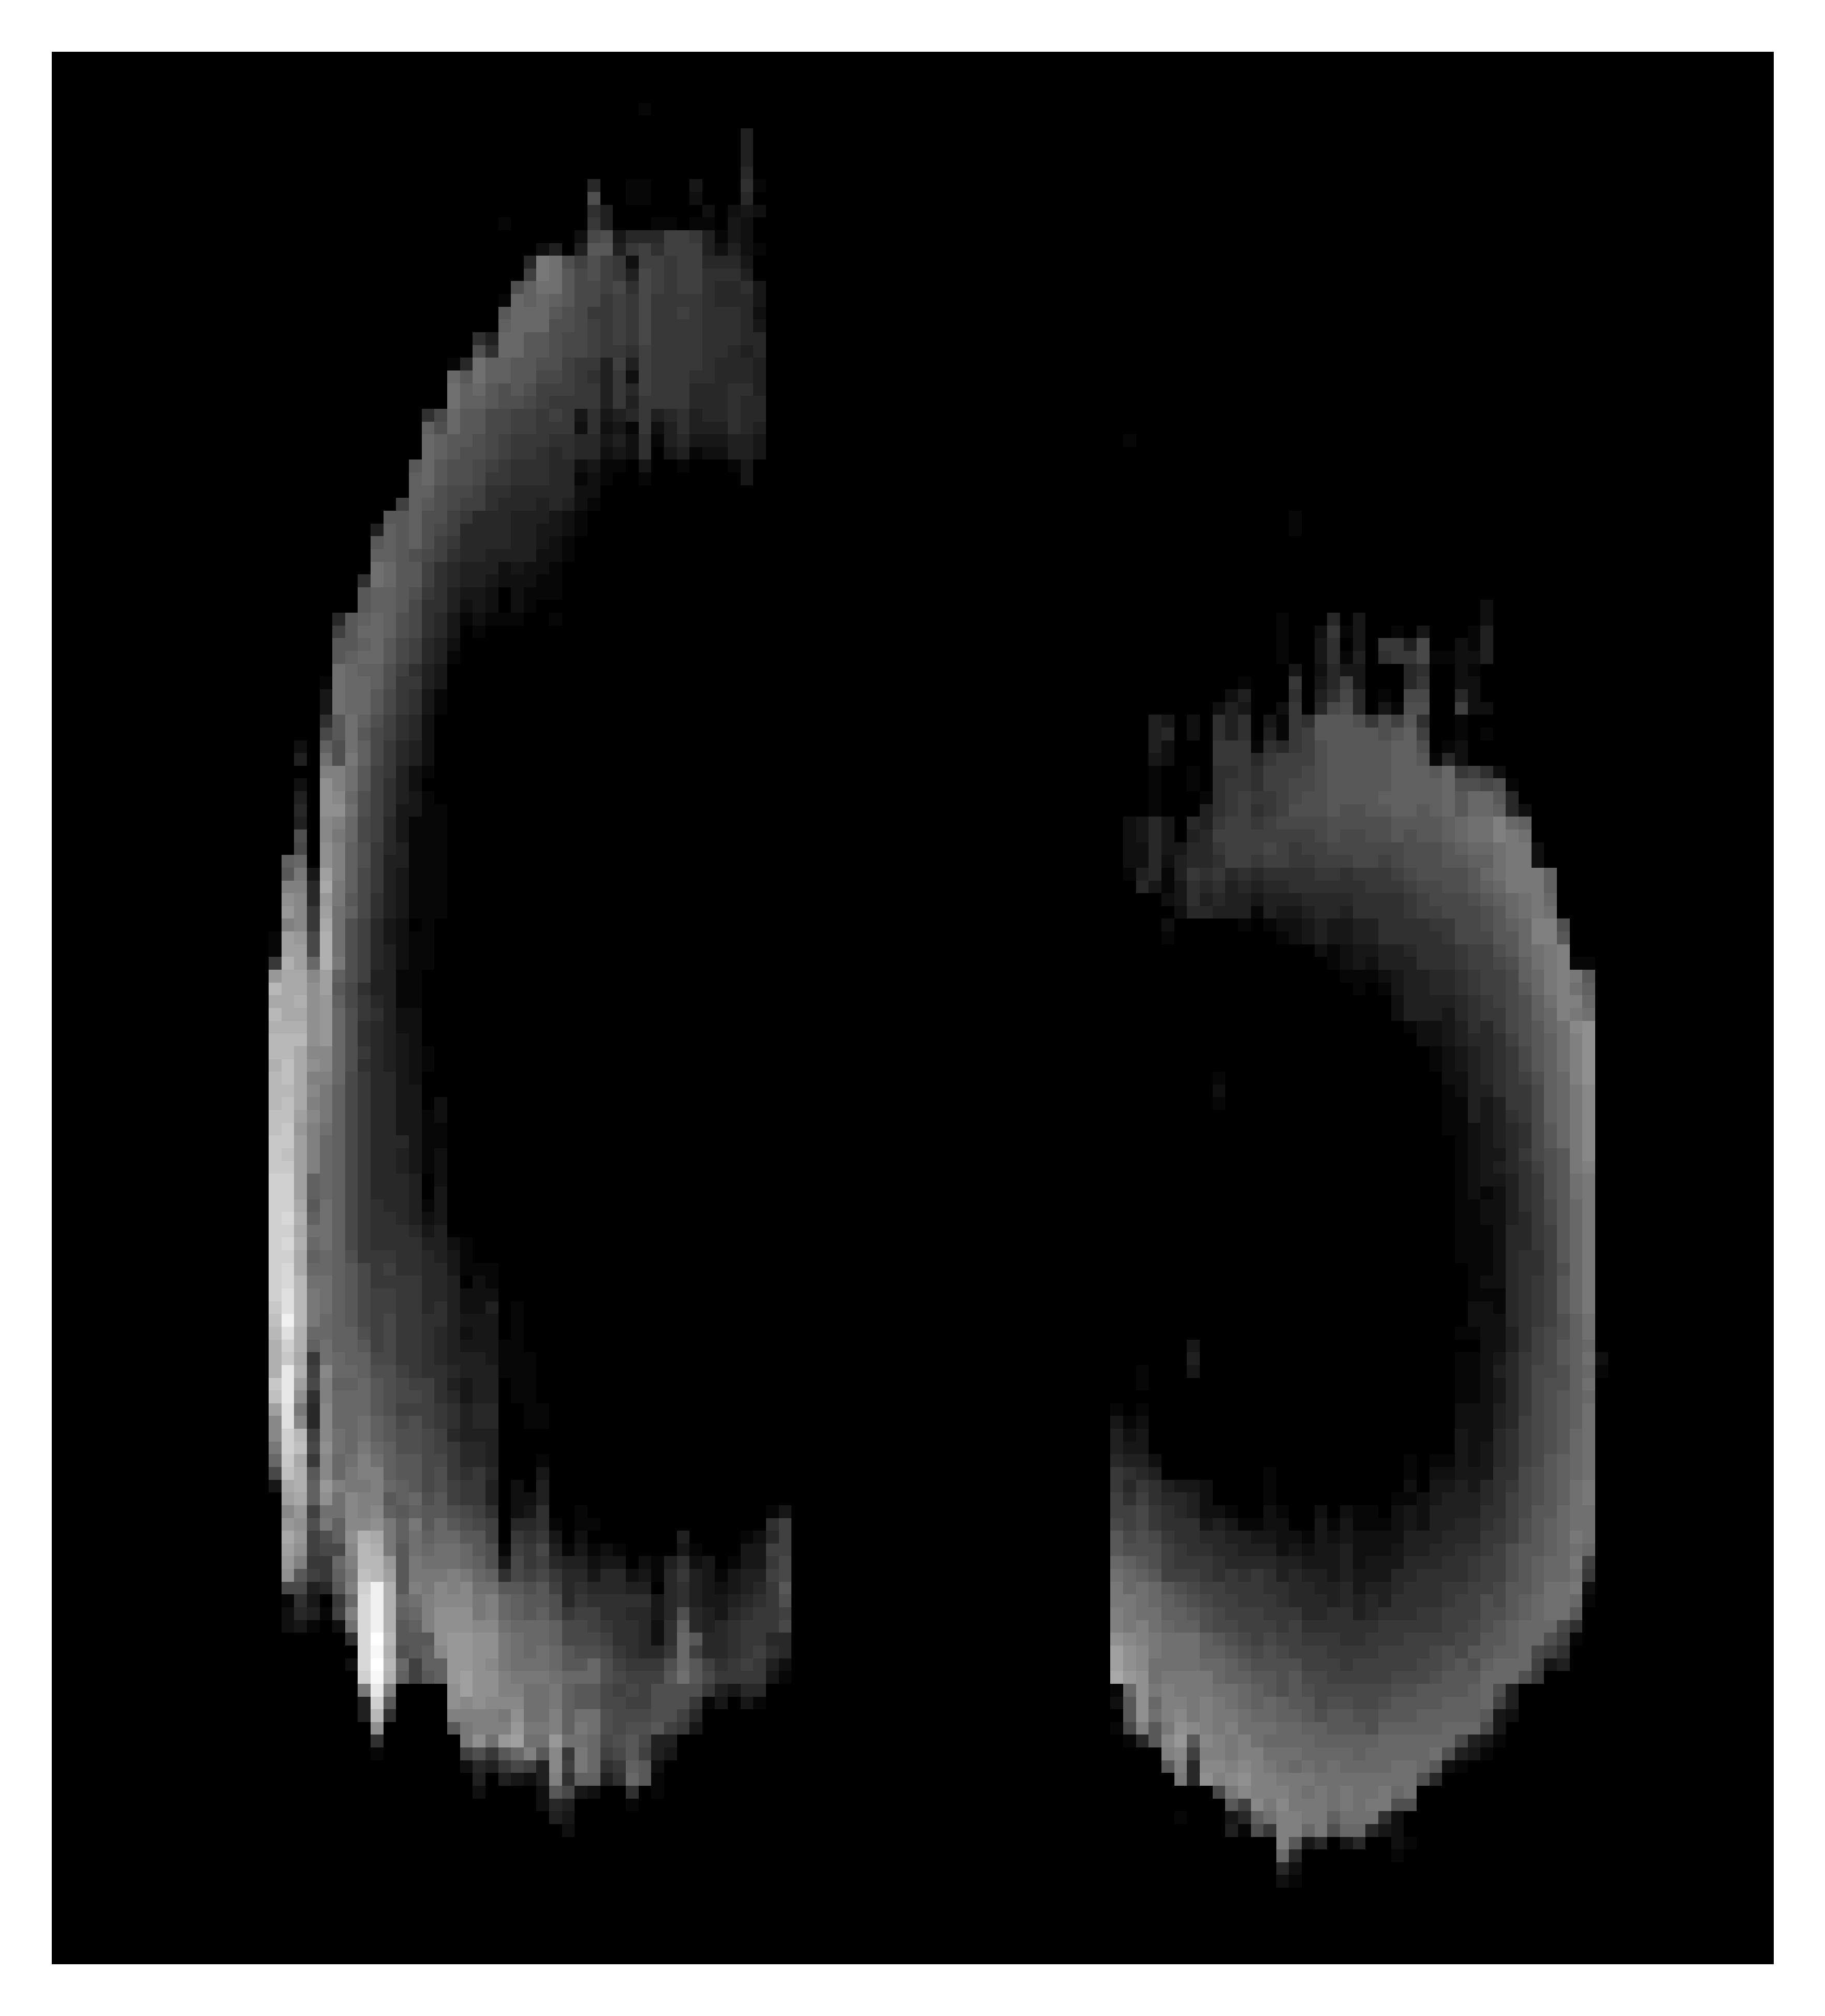

Figure 4: Two atypical examples from the test dataset that visually compare the masks predicted by the segmentation models investigated with the ground truth. In (a), a ground truth mask is shown where the medial meniscus was separated into two (white arrow). (b-d) are the generated masks from SAM 1, SAM 2, and 3D U-Net respectively. (e) shows a test case with what appears to be a partial meniscectomy on the posterior medial meniscal horn (white arrow). (f-h) are again the generated masks from SAM 1, SAM 2, and 3D U-Net respectively. All images in this figure were created by summing the 3D masks through the inferior-superior axis of the body, as if looking down on the mask from above. The brighter a pixel, the thicker the meniscus in this transverse position.

Two selected cases from the test set, and the corresponding model predictions, are shown in Fig. 4. One abnormal case in the test set contained a medial meniscus that was fully separated in the middle (a). The models were only exposed to a single case in the train set with a similar morphology. Predicted masks for this test case are shown in (b-d). It can be seen that, despite only being exposed to one similar case in training, 3D U-Net correctly reproduces the two fully-detatched medial meniscus segments. Both SAM configurations struggle to replicate this feature. Another example was selected due to what appears to be a partial meniscectomy on the posterior horn of the medial meniscus (white arrow in 4(e)). The predicted masks for this case indicate that SAM 1 fails to recognise this feature, while SAM 2 and 3D U-Net both do. This demonstrates that training SAM end-to-end improved the ability of the model to extract anomalous morphological features of menisci.

Fig. 5 displays surface mesh representations of masks generated from a test set image by SAM 2 and U-Net, along with the corresponding ground truth. The 3D meshes were produced using ITK-SNAP. Both SAM 2 and U-Net scored the lowest Dice coefficient on this image, so the meshes are a good example of where SAM 2 and U-Net fail to accurately perform meniscus segmentation. The first feature to highlight is that SAM 2 fails to replicate the narrowing near the middle of the medial meniscus. U-Net does much better at reproducing the general geometry of the ground truth. SAM 2 also struggles to keep the menisci as a contained volume, with flecks of unattached positive predictions seen in Fig. 5(b). U-Net did not suffer from this problem, which likely stemmed from SAM 2 lacking 3D contextual information unlike the former.

SAM configurations often outputted masks containing small isolated islands of positive prediction (e.g. Fig. 5(b)), struggling to output consistent intact volumes. Through performing connected component analysis on the ground truths and generated masks, it was seen that predictions from SAM 1 and 2 contained an average of 46.946.946.946.9 and 10.210.210.210.2 components respectively, compared to the ground truths which contained an average of 2.12.12.12.1. In contrast, masks generated by 3D U-Net contained very few regions disconnected from the main segmentation bodies (average number of connected components of 2.32.32.32.3). This is desirable, because less post-processing would be required if the generated masks were to be analysed geometrically.

Figures 4 and 5 show that the masks generated by 3D U-Net are smoother, whereas the texture of the SAM masks more closely matches the ground truth. This could be due to the ground truths being annotated slice-wise leading to staircase artifacts that are not faithful 3D representations of the menisci. In this case, the Dice score may be punishing the 3D U-Net model for generating smoother masks than the ground truths, which may actually more closely resemble the true 3D structure of the menisci. There was concern that this smoothing effect might result in 3D U-Net smoothing out smaller features, but the Hausdorff distance results show that the smoothing is not compromising the model’s ability to match the meniscus geometry.